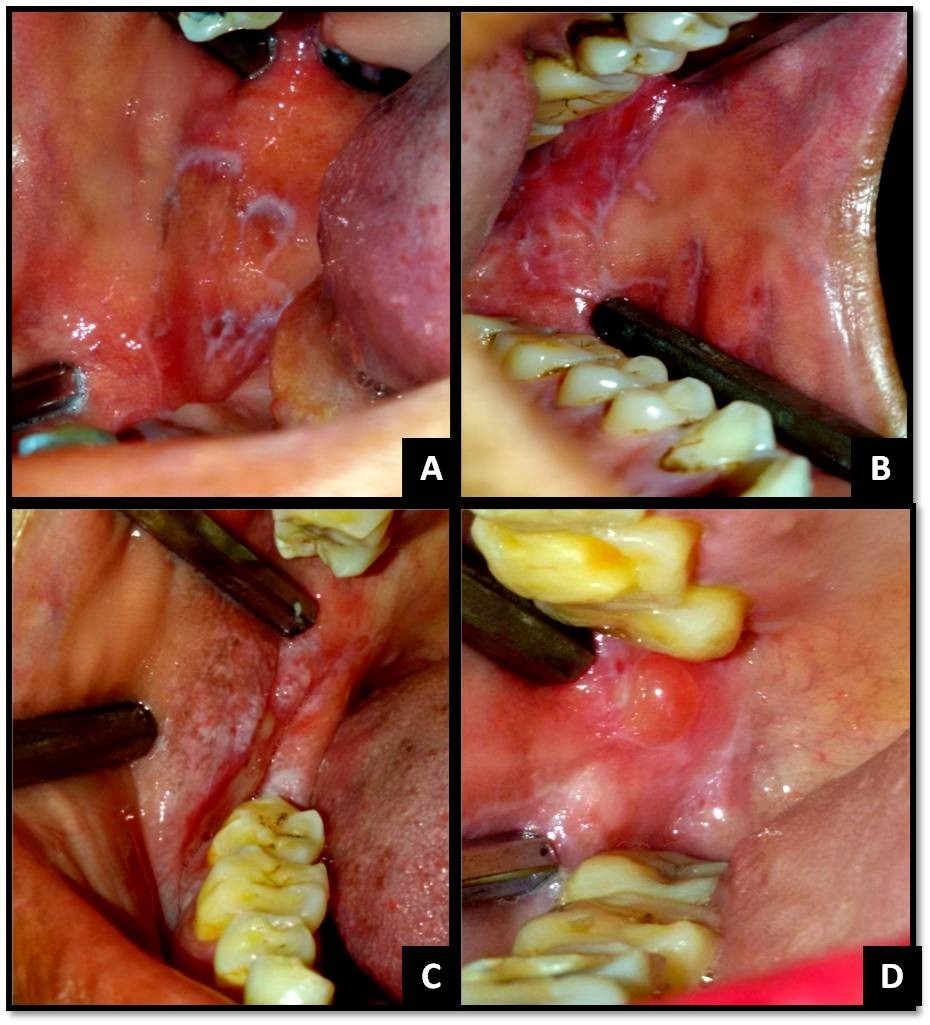

The clinical diagnostic criteria for oral lesions used in this study was- 1. The presence of keratotic, pinhead-sized, white, slightly elevated papules (papular lichen planus), which may be discrete or arranged in reticular (reticular lichen planus) or plaque-like (plaque-like lichen planus) configurations. 2. Atrophic lichen planus, characterized by thinning of the epithelium leading to the appearance of atrophic red areas within the white lesions. 3. Erosive (ulcerative) lichen planus, characterized by areas of well-defined ulceration within the above mentioned lesions. 4. Bullous lichen planus, characterized by the presence or development of bullous areas within the above mentioned lesions.1,2Representative images of OLP are shown in Figure 1 and Figure 2.

Figure 1.(A) Reticular OLP on right buccal mucosa; (B) Reticular OLP on left buccal mucosa; (C) Erosive and papular OLP on right buccal mucosa and vestibule; (D) Bullous OLP on right buccal mucosa;

(A) Reticular OLP on right buccal mucosa; (B) Reticular OLP on left buccal mucosa; (C) Erosive and papular OLP on right buccal mucosa and vestibule; (D) Bullous OLP on right buccal mucosa;